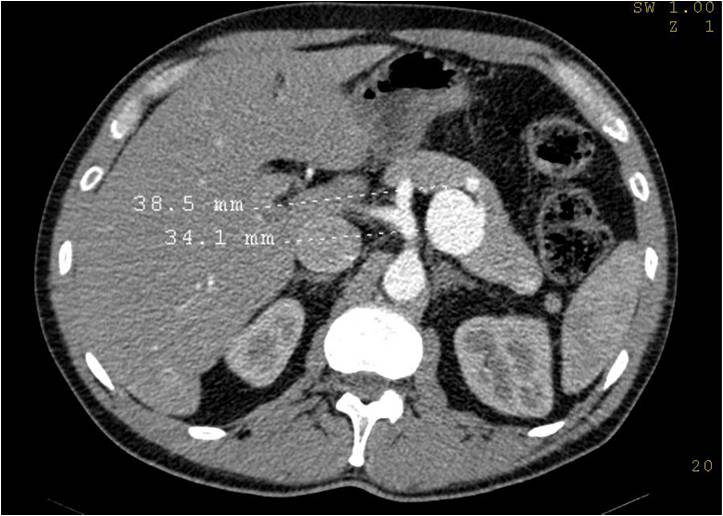

脾动脉瘤:窄颈动脉瘤栓塞可以无需球囊或支撑架辅助弹簧栓子栓塞

用5F导管很容易进入腹腔动脉和脾动脉。不需要微导管。普通0.035导丝引进。

脾动脉瘤填塞:动脉瘤囊填塞技术

脾动脉中段动脉瘤 |

用普通导管选择性进入瘤囊内 |

释放普通(0.035'')弹簧栓子入瘤囊内 |

栓塞后保留载瘤动脉开放 |

配合可控弹簧圈封口,减低患者费用。